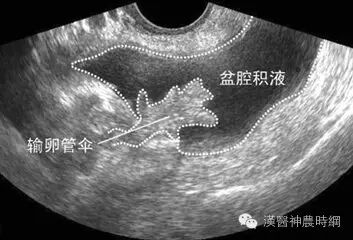

8盆腔积液——3厘米以下不用治

“盆腔积液”听起来非常可怕,其实人体的盆腔、腹腔并不是干巴巴的一块“土地”,腹膜、大网膜、肠管等都会分泌一些液体,这些液体通常起到润滑和保护盆腹腔器官和组织的作用。

而“盆腔积液”仅是一种表现,而不是一种疾病,更确切地说是影像学对盆腔内液体的一种描述。

医生说中国医科大学附属第一医院妇科主任张颐介绍,几乎每个女性都会有不同程度的盆腔积液,一般女性都在3厘米以下。3厘米以下可以视为正常范围,如果没有其他不舒服的症状,是不需要治疗的。

“那如果稍微多于3cm呢?”如果是排卵期、月经期或者月经刚结束的时候,积液可能会略有增多,但如果没有其他任何异常,即使稍微多于3cm也不必大惊小怪。